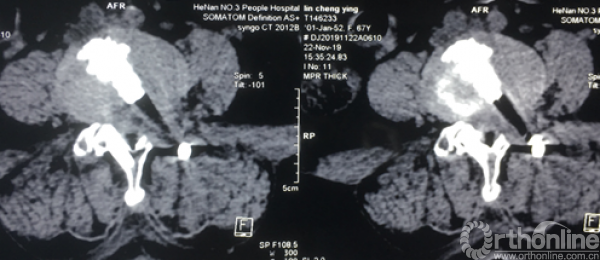

术前CT示:1.腰椎退行性变;2.L4椎体滑脱;3.腰椎管狭窄症;4.相应神经根硬膜囊受压。

术前CT

术前腰椎核磁共振横断面

术后三维SCT确认融合器,钉棒植入位置满意

术后三维SCT重建